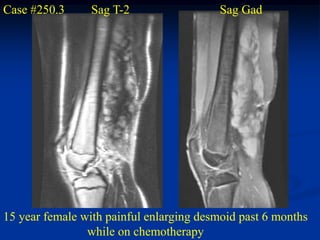

Case #250.3      Sag T-2                 Sag Gad

15 year female with painful enlarging desmoid past 6 months

while on chemotherapy

Coronal Gad shows minimal response to chemotherapy